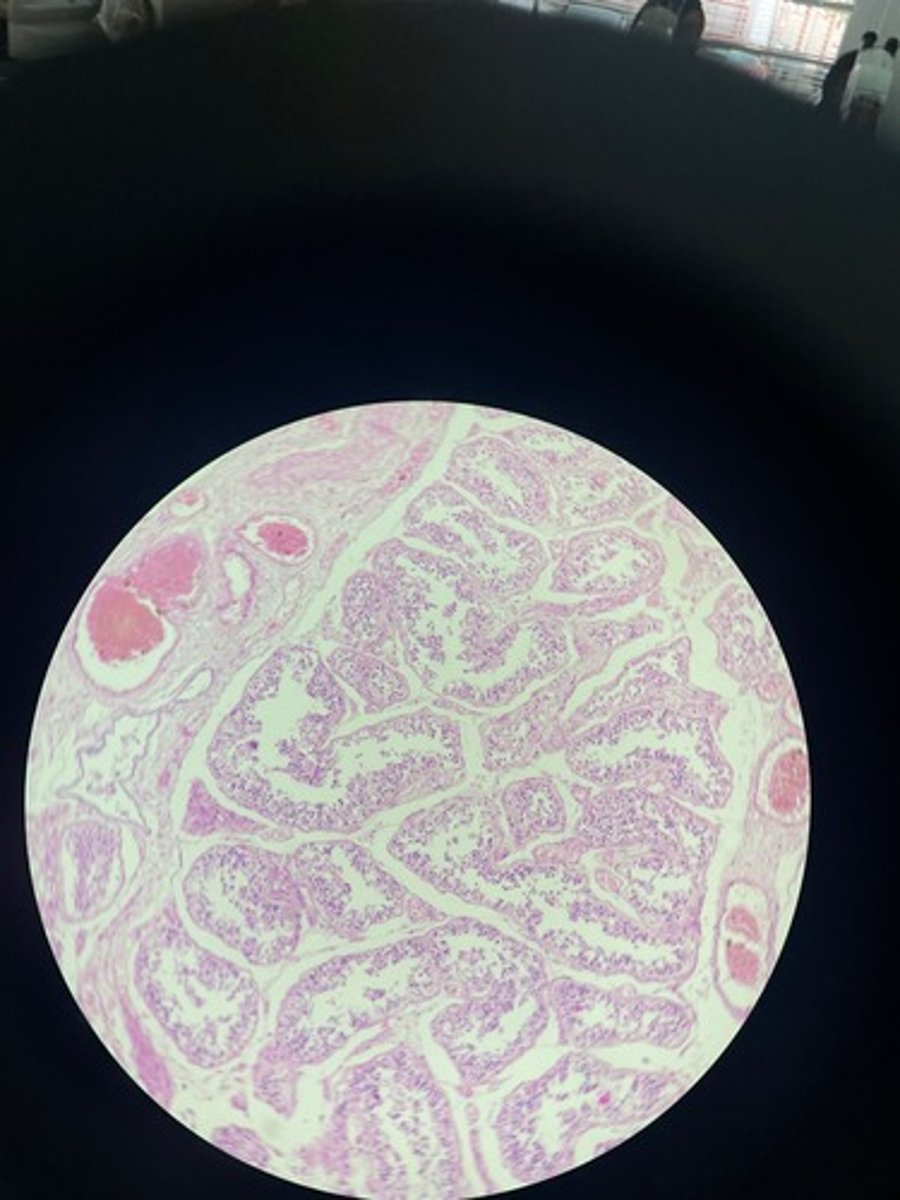

Thymus HE

Thymus HE

Thymus HE

Thymus HE

Thymus HE

Thymus HE

Thymus HE

Thymus HE